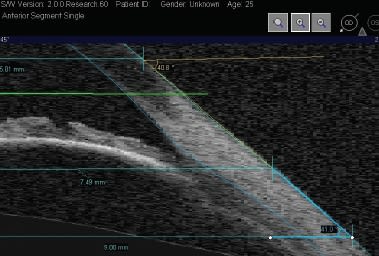

We decided to take this one step further, again using anterior segment OCT. In our Pacific University College of Optometry studies, the corneal-scleral tangential angle between 10.00mm and 15.00mm (defined in our study as the limbal angle) was measured as well as the angle from 15.00mm to 20.00mm (the scleral angle) (Figure 4).

Figure 4. Limbal and scleral angle position illustration with the OCT in the nasal-inferior direction of an left eye in a study subject.

Figure 6. Example of a tangential limbal and anterior scleral shape OCT image, with a 41 degree limbal and scleral angle (steep profile) in the 225 degree direction.